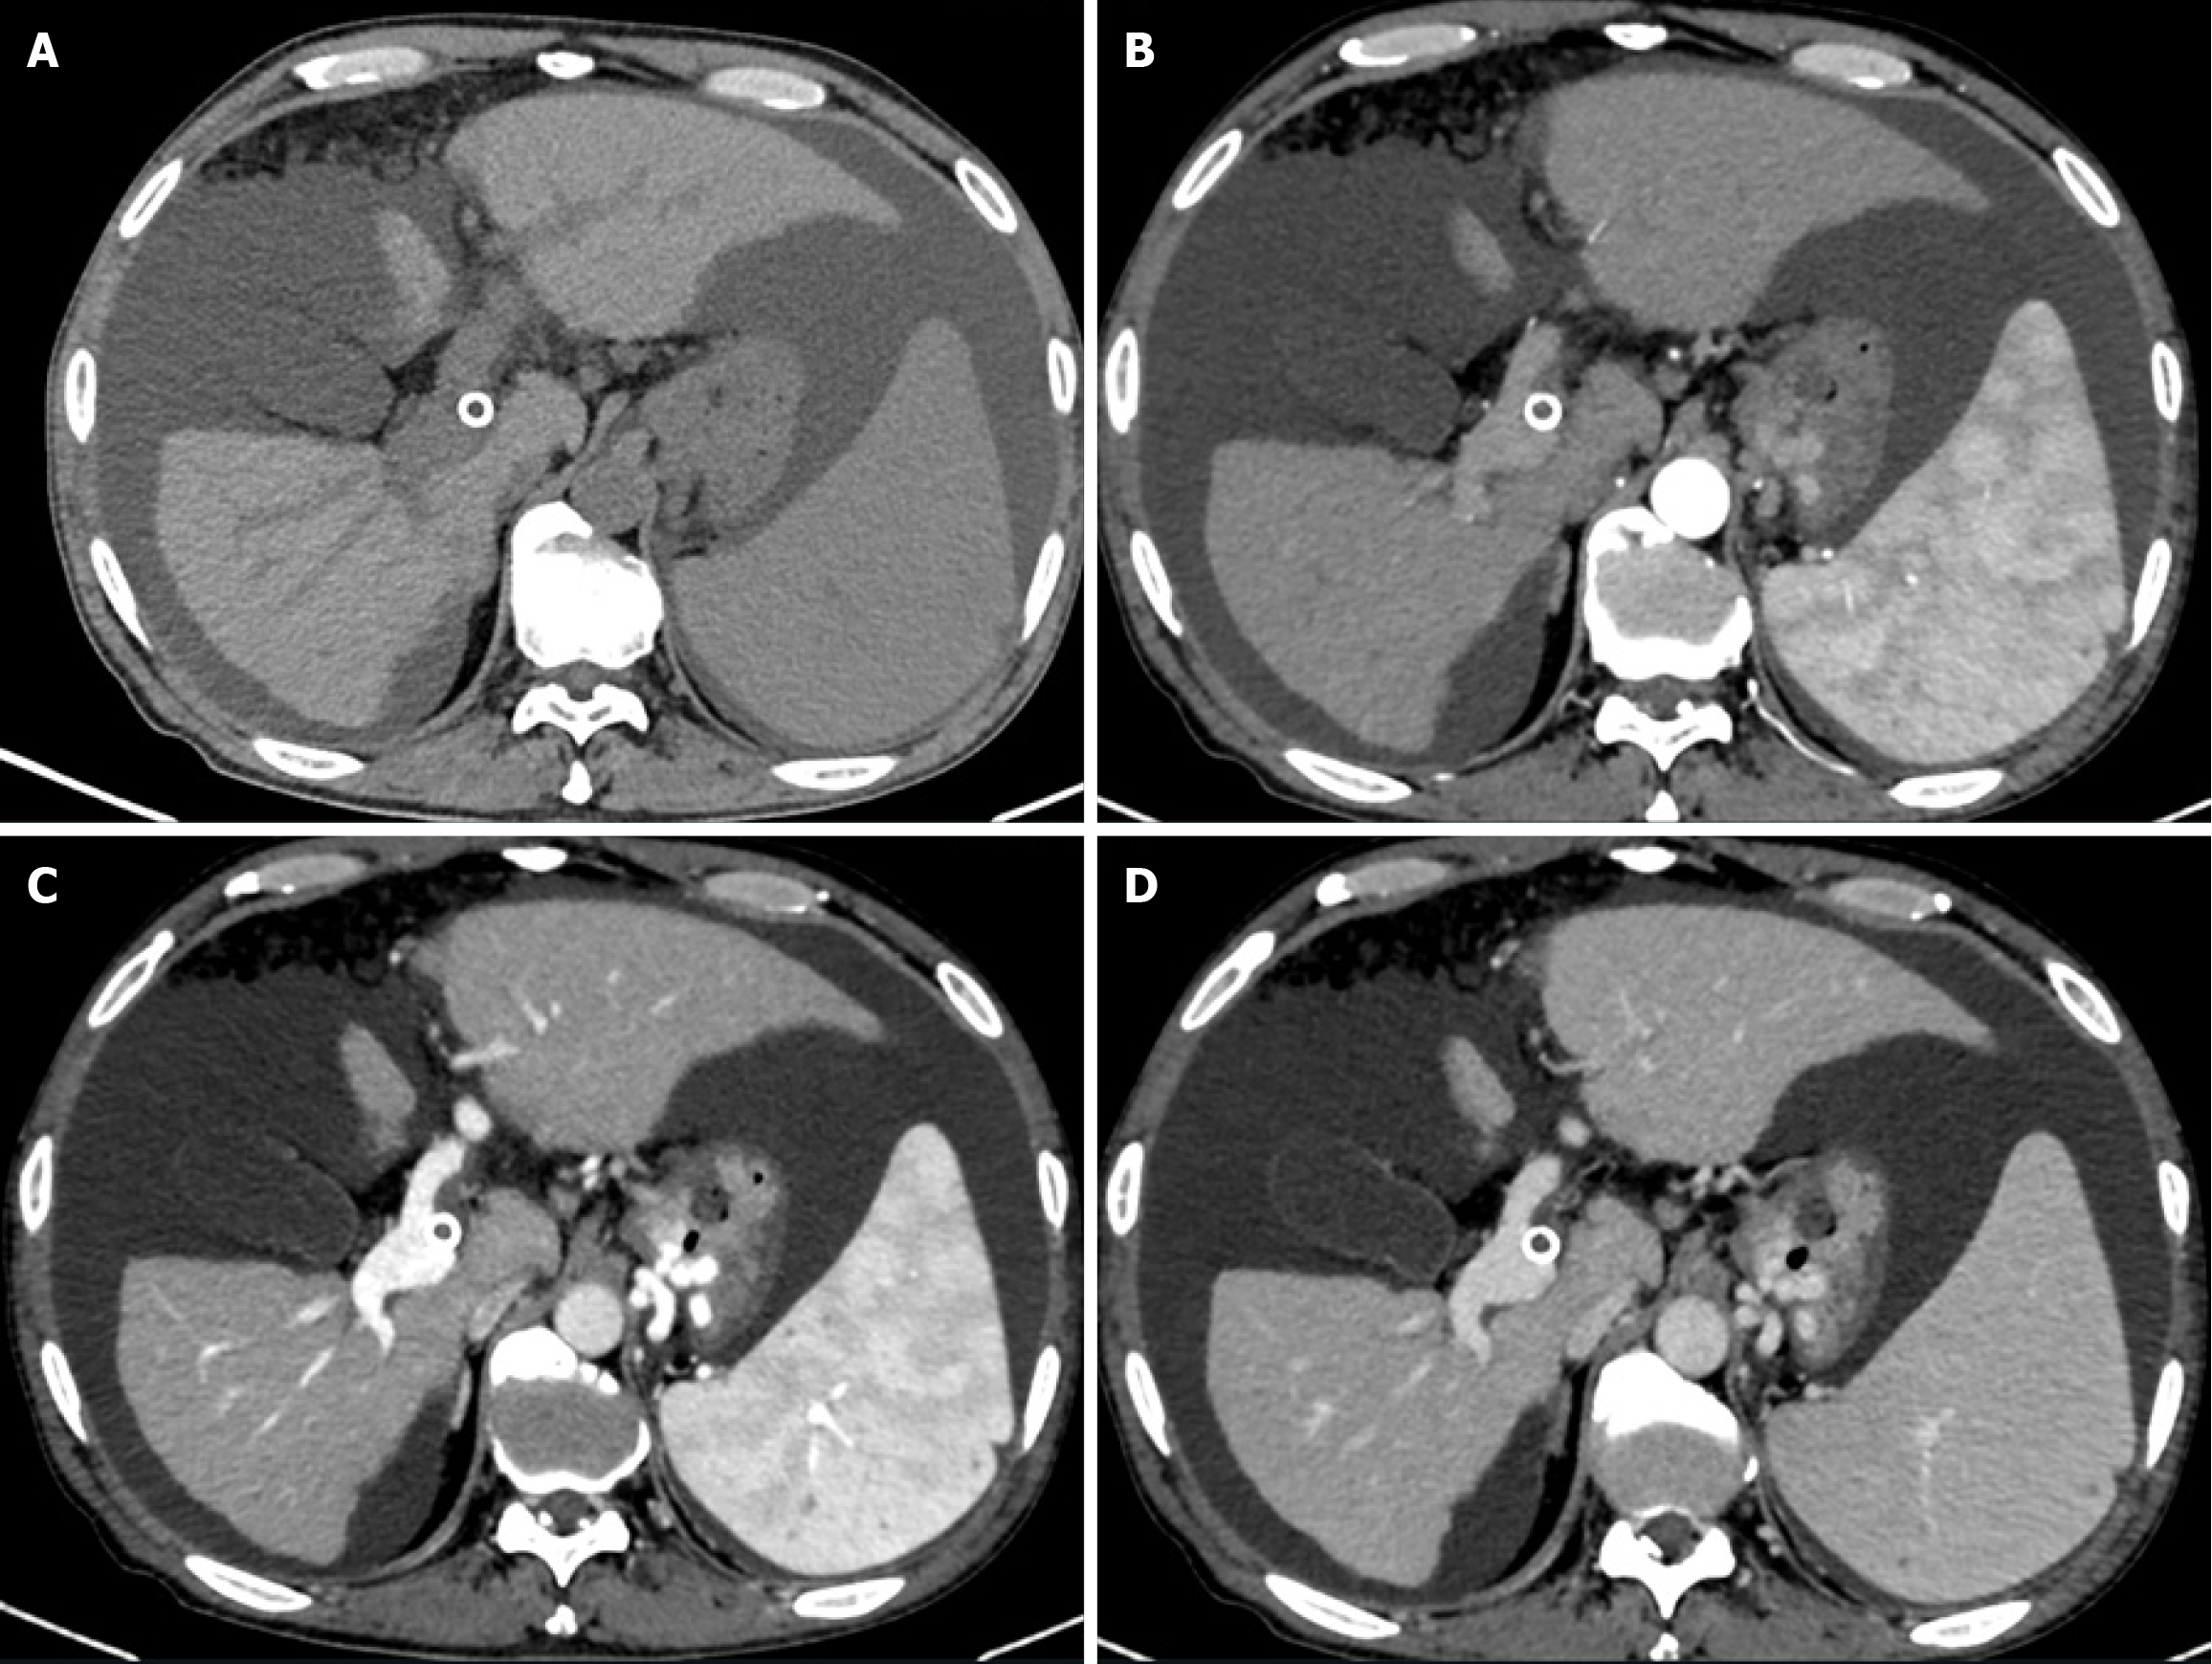

Gastroscopy examination showed severe varices in the mid and lower esophageal segments and gastric fundus, indicating portal hypertension-related gastric disease (Figure 1). Abdominal computed tomography (CT) examination revealed cirrhosis, splenomegaly, portal hypertension with collateral circulation formation, and a small amount of mural thrombosis in the main portal vein, superior mesenteric vein, and splenic vein (Figure 2).